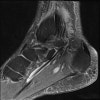

MRI : 장무지굴근건 건초염(Flexor hallucis longus tenosynovitis)